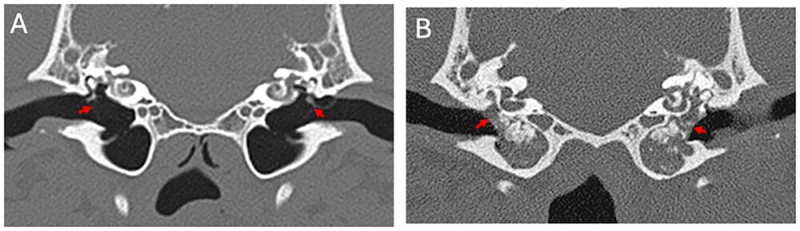

Deep learning models trained on scan images can aid vets in managing caseloads. AI tools can support vets in diagnosing disease, research has shown.A computer model has been trained to recognise a common disease in dogs with an encouraging success rate, underscoring its potential as a veterinary tool.The approach supports the use of AI for relatively straightforward tasks, to allow vets to concentrate on more complex tasks, according to the team behind the study. Scan images Researchers from the Royal (Dick) School of Veterinary Studies, the Roslin Institute and the University of Edinburgh’s School of Informatics developed their model using CT scan images of dogs’ middle ears – a part of the ear that is frequently affected by disease.The model was trained to recognise disease using about 500 images, some that showed signs of disease and others that did not, which had been manually interpreted by veterinary experts. This number is fewer than the several thousands that would typically be needed for many AI studies, which would be resource-intensive to generate.The AI tool was able to make correct diagnoses in 85 per cent of cases. Experts say the result is robust for a relatively small sample size, demonstrating the validity of the approach, and could be improved if additional images were annotated. AI can be deployed to diagnose disease with reliable accuracy. Diagnosis potential The application of AI in this way, which is established in human medicine, could be made to various veterinary medicine challenges, potentially including those that are traditionally difficult to diagnose by eye. This would save time and money in making diagnoses, the team says.A bank of veterinary medical images, annotated by vets, would be required to enable adoption of AI in veterinary diagnoses, and could be applied across a range of conditions, the team suggests. Vet schools and hospitals such as the R(D)SVS have banks of images, but a sufficient number have to be annotated to train algorithms.The study was conducted by a masters degree student in the School of Informatics. Our study showed that deep learning computer models can be trained to determine whether or not disease is present in a veterinary CT image. Even training our model on a relatively small number of images had encouraging results.This outcome is a call to arms to gather resources to enable models of this type, for various veterinary conditions. Dr Chris Banks, Roslin Institute This is a great example of how AI can be put to use to help veterinarians, rather than replace them. Dr Tobias Schwarz, Royal (Dick) School of Veterinary Studies This article was first published by the Royal (Dick) School of Veterinary Studies on 10 September 2025 Related links Link to paper The Royal (Dick) School of Veterinary Studies The Roslin Institute Publication date 09 Sep, 2025